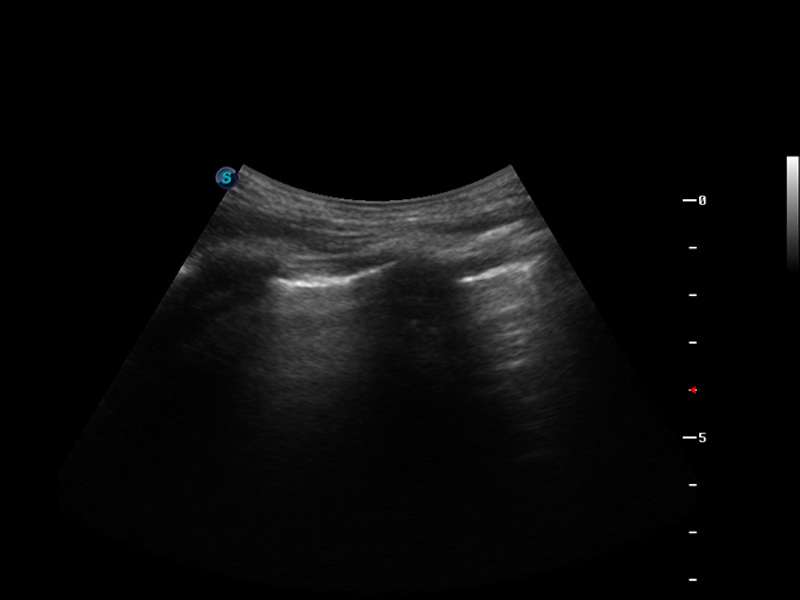

μ-Scan微米成像